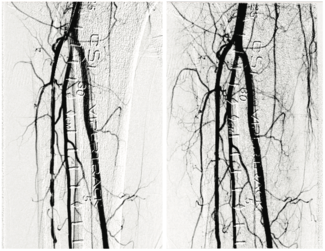

Vishal Kapur, MD, FACC, FSCAI, RPVI

We have been using the Highlander™ 014 PTA Balloon Dilatation Catheter since it came out in early 2023. It is a great balloon because of its deliverability, non-compliance, and ability to expand in a controlled, uniform manner.